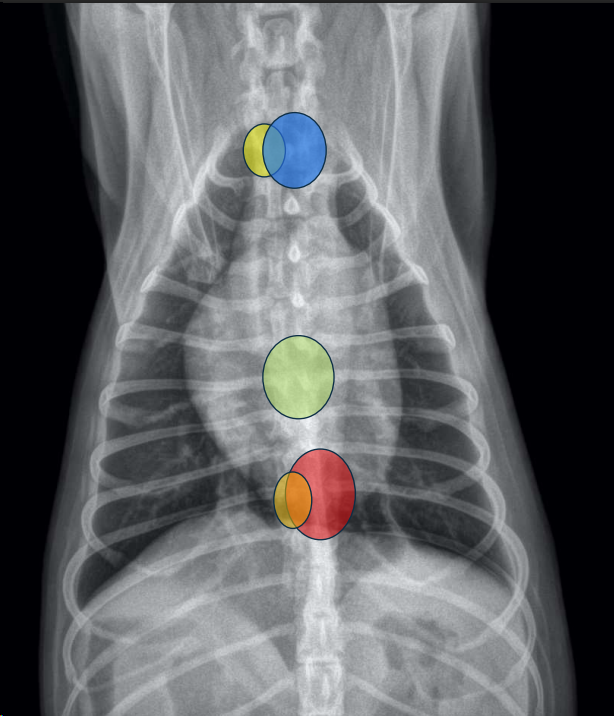

CLASIFICACIÓN DE MASAS MEDIASTÍNICAS

Craneodorsales: alteraciones esofágicas, aneurisma aórtico, hematoma, tumor base cardíaca/neurogénico, absceso, granuloma, lesión vertebral.

Hiliares/Perihiliares: alteraciones esofágicas, tumor base cardiaca, linfoadenopatía traqueobronquial, masa tiroidea ectópica.

Caudodorsales: hernia paraesofágica, tumores neurogénicos, granulomas.

Craneoventrales: linfoma, timoma, tumor tiroideo, histiocitosis, lipoma, fibrosarcoma, linfoadenopatía esternal o craneal, absceso, aneurisma auricular.